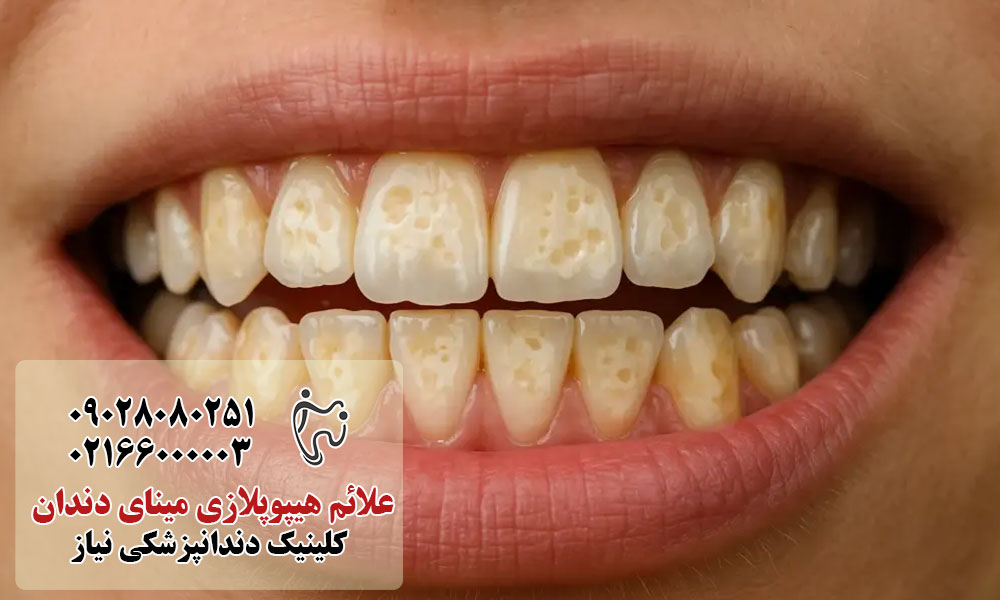

علائم و نشانههای هیپوپلازی مینای دندان

هیپوپلازی مینای دندان میتواند با علائم مختلفی ظاهر شود که شدت آنها بسته به میزان نقص مینای دندان متفاوت است. این نشانهها معمولاً پس از رویش دندانها قابل مشاهده هستند و در صورت بیتوجهی میتوانند به مشکلات جدیتری منجر شوند.

مهمترین علائم و نشانهها عبارتاند از:

- تغییر رنگ دندانها: مشاهده لکههای سفید، زرد یا قهوهای روی سطح دندان که اغلب مرز مشخصی دارند.

- نازک بودن مینای دندان: دندانها ظاهری شکنندهتر داشته و لایه مینا نسبت به حالت طبیعی ضخامت کمتری دارد.

- ناصافی، شیار یا حفره روی دندان: وجود فرورفتگیها، خطوط یا سطح زبر روی مینای دندان که بهراحتی با زبان احساس میشود.

- حساسیت دندانی: درد یا ناراحتی هنگام مصرف غذاها و نوشیدنیهای سرد، گرم، شیرین یا اسیدی.

- افزایش خطر پوسیدگی دندان: بهدلیل ضعف لایه محافظ مینا، دندانها سریعتر دچار پوسیدگی میشوند.

- درد یا ناراحتی مداوم دندان: بهویژه در موارد شدید که لایههای زیرین دندان در معرض عوامل خارجی قرار میگیرند.

- مشکلات زیبایی لبخند: ظاهر نامطلوب دندانها که میتواند بر اعتمادبهنفس فرد، بهخصوص در کودکان و نوجوانان، تأثیر بگذارد.

تشخیص بهموقع این علائم و مراجعه زودهنگام به دندانپزشک نقش مهمی در کنترل عوارض هیپوپلازی مینای دندان دارد.